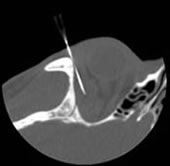

CT (computed tomography) guided biopsies are done percutaneously when lesions are not palpable and cannot be done in the clinical setting. CT guided biopsies offer a noninvasive alternative to open surgical biopsies.

The image to the right shows a needle placed inferior to the foramen ovale. The second case below shows an orbital lesion that was biopsied with a fine needle technique.